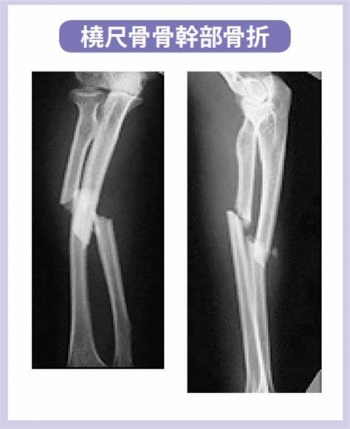

橈・尺両骨骨幹部骨折

橈・尺両骨骨幹部骨折は、単独骨折より完全整復が困難。

そのため、骨癒合が伸びたり、偽関節形成の割合が高くなる

また、後遺症として、変形治癒、前腕回旋障害、阻血性拘縮なども起こることがあります。